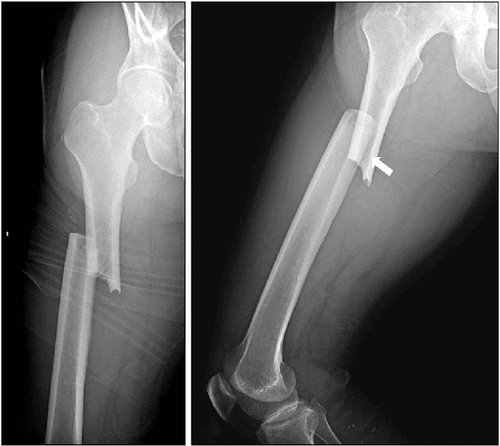

Stress Fracture - विशिष्ट भागावर नेहमी दबाव किंवा ताण पडून तुटणे. हे फ्रॅक्चर खेळाडूंमध्ये जास्त आढळून येते.